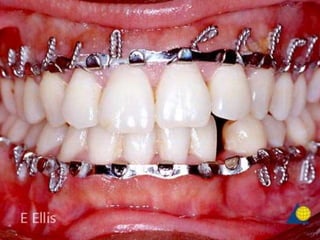

• #31 The occlusion was reestablished with MMF. A reconstruction plate was then adapted and secured to provide load-bearing fixation across the fracture gap.. Particulate autogenous bone was placed into the fracture gap and the incision closed in layers.

• #39 Intraoperative photograph showing malunion of left parasymphyseal fracture. Rt angle region

• #40 angle osteotomy and fixation with two miniplates.